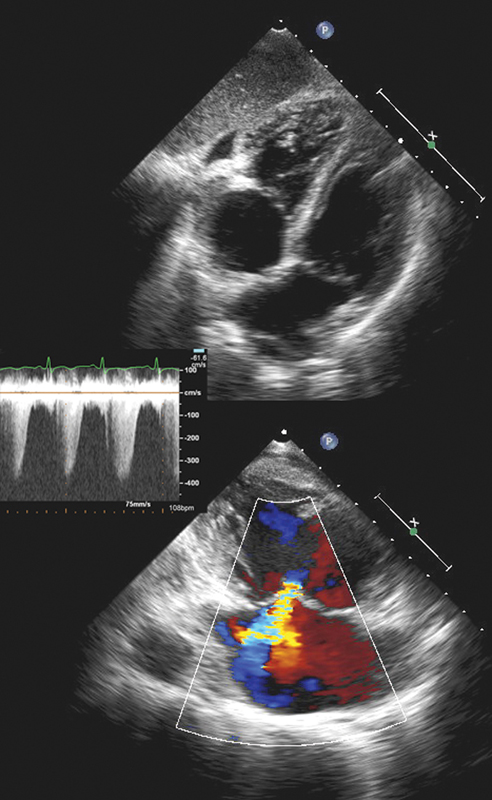

فحوصات تشخيصية لبعض امراض القلب والشرايين التاجية